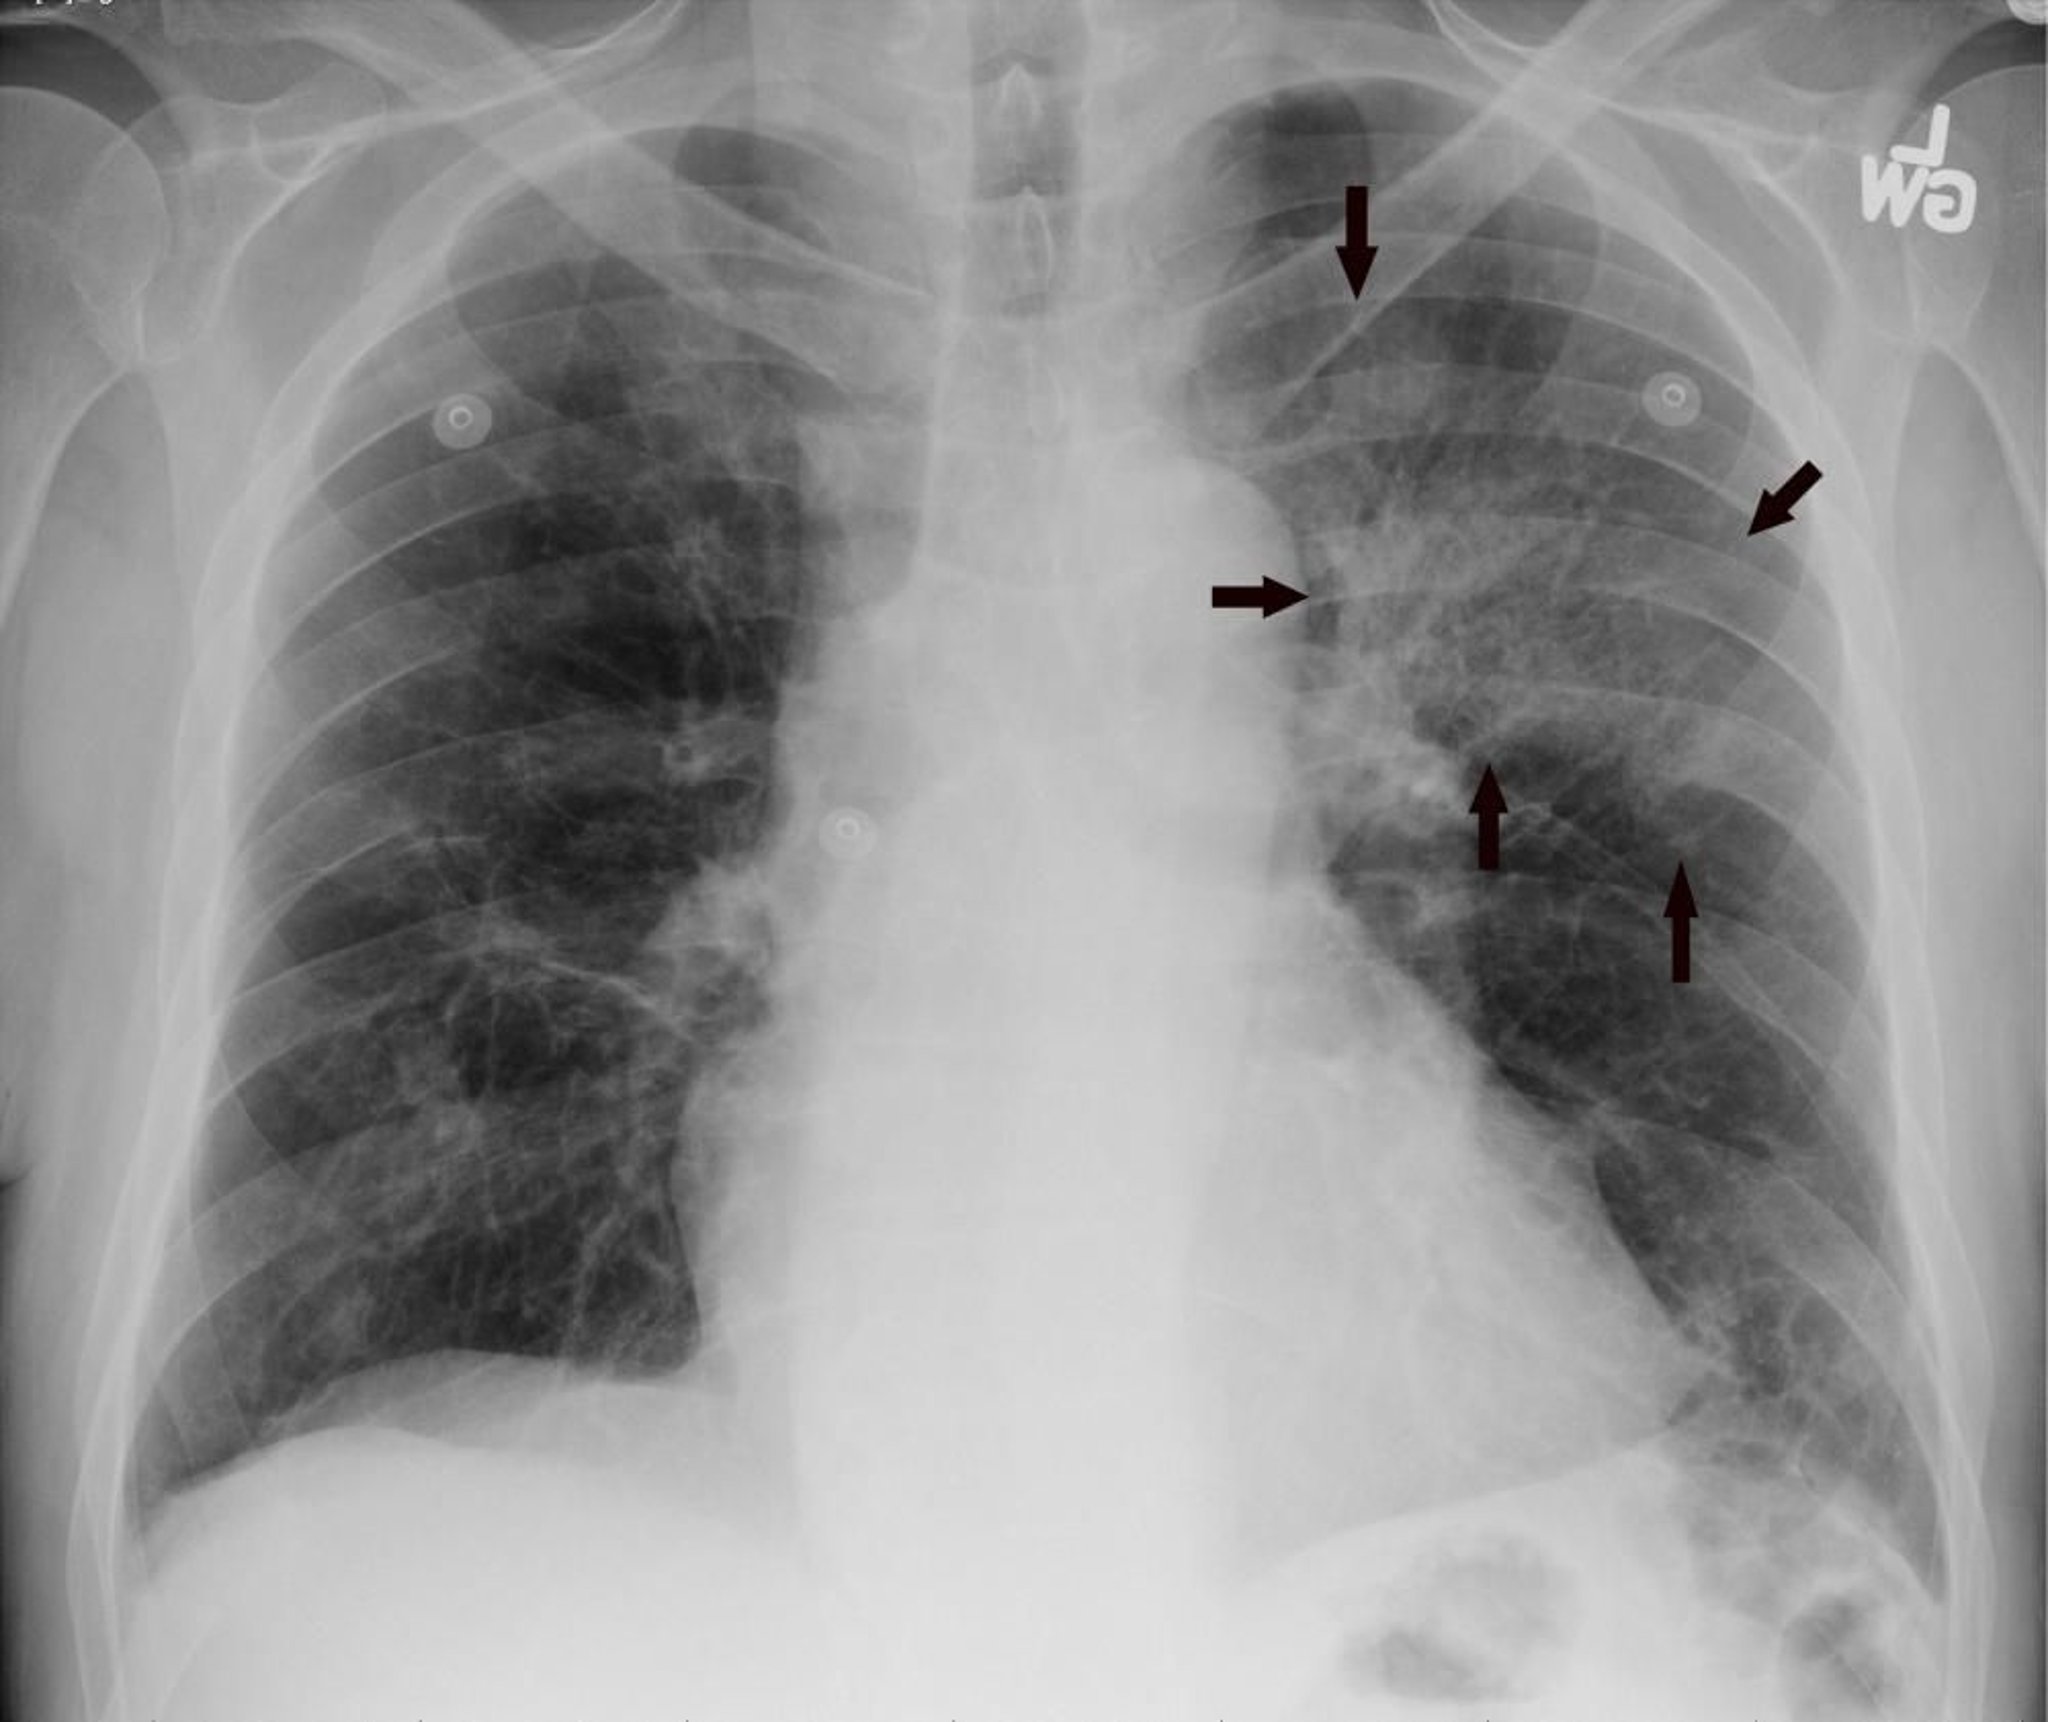

Die posteroanteriore Röntgenaufnahme des Thorax zeigt ein Infiltrat des linken Oberlappens, das auf eine Pneumonie hinweist (Pfeile).